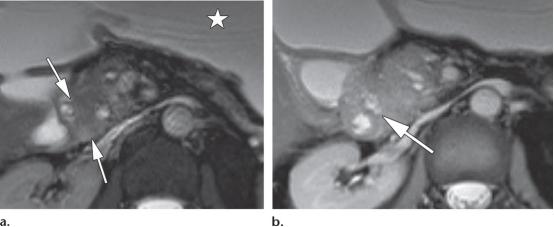

42岁男性,2型自身免疫性胰腺炎

(a图)轴位T2WI示胰腺近端边界不清的等信号肿块样病变(白色长箭头)

(b图)冠状位T2WI示胰管管径变窄,并横穿同一区域(白色长箭头),注意观察胆总管远端的局灶性狭窄(白色短箭头)

(c图)轴位增强延迟期磁共振示同一区域的局灶性肿物样病变(白色短箭头),其余胰腺未见明确异常。